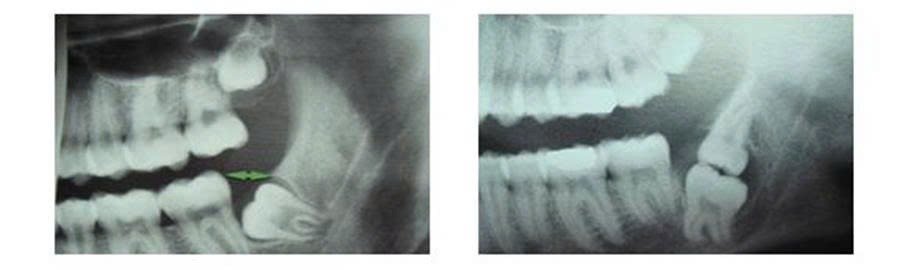

Hình 2. Răng khôn hàm dưới và răng khôn hàm trên mọc lệch, ngầm.

3.3. Sâu răng hàm lớn thứ hai và sâu chính răng khôn.

- Khi răng khôn mọc lệch gần, nó còn gây sâu răng hàm lớn thứ hai (thường là sâu mặt xa) và sâu chính răng khôn. Nguyên nhân do lắng đọng thức ăn dưới lợi trùm và khe giữa răng hàm lớn thứ hai và răng khôn.

Hình 5. Hình ảnh Xquang răng khôn mọc lệch gần gây sâu răng hàm lớn thứ 2 và sâu chính răng khôn

Tổn thương răng hàm lớn thứ hai thường rất hay bị bỏ qua. Ban đầu, người bệnh chỉ thấy mắc thức ăn, gây khó chịu khi vệ sinh răng miệng. Dần dần, người bệnh thấy ê buốt khi ăn nóng lạnh, chua ngọt rồi tự hết. Tổn thương sâu mặt xa răng hàm lớn thứ hai nhiều khi phải chụp X.Quang mới phát hiện được. Đến khi triệu chứng đã rõ ràng, người bệnh đến khám thì tổn thương sâu đã lớn, có thể phải điều trị tủy hoặc thậm chí phải nhổ răng.

Kế hoạch điều trị: tùy mức độ tổn thương sâu răng hàm lớn thứ 2, có thể hàn răng sâu sau khi nhổ răng khôn.

Viêm tủy, viêm quanh cuống răng hàm lớn thứ 2 chưa có chỉ định nhổ: nhổ răng khôn, điều trị tủy răng hàm lớn thứ 2, làm chụp răng hàm lớn thứ 2. Trong trường hợp răng khôn lệch không nhiều, chưa bị tổn thương, chân răng tốt có thể bảo tồn răng khôn

Răng hàm lớn thứ 2 có chỉ định nhổ, răng khôn lung lay nhiều hoặc vỡ thân không có khả năng làm trụ khi làm răng giả: nhổ răng hàm lớn thứ 2, răng khôn, phục hình. Nếu răng khôn còn vững chắc, có khả năng điều trị bảo tồn thì có thể giữ làm trụ cho cầu răng hàm lớn thứ nhất-hai-khôn.

3.4. Tiêu xương nâng đỡ của răng số hàm lớn thứ hai.

Nguyên nhân là do răng khôn mọc lệch thúc vào tổ chức xương nâng đỡ phía xa của răng hàm lớn thứ hai gây tiêu xương. Do vậy, cần nhổ răng khôn trước khi tổ chức xương nâng đỡ của răng số hàm lớn thứ hai bị tiêu, tránh gây lung lay và buốt răng hàm lớn thứ hai sau khi nhổ răng khôn. Những trường hợp phía xa chân răng hàm lớn thứ hai bị tiêu nhiều, khi nhổ răng khôn, nên ghép xương và màng sinh học để có thể phục hồi lại phần xương ở phía xa chân răng hàm lớn thứ hai.

Hình 7. Răng khôn mọc lệch gần gây tiêu xương phía xa răng hàm lớn thứ hai